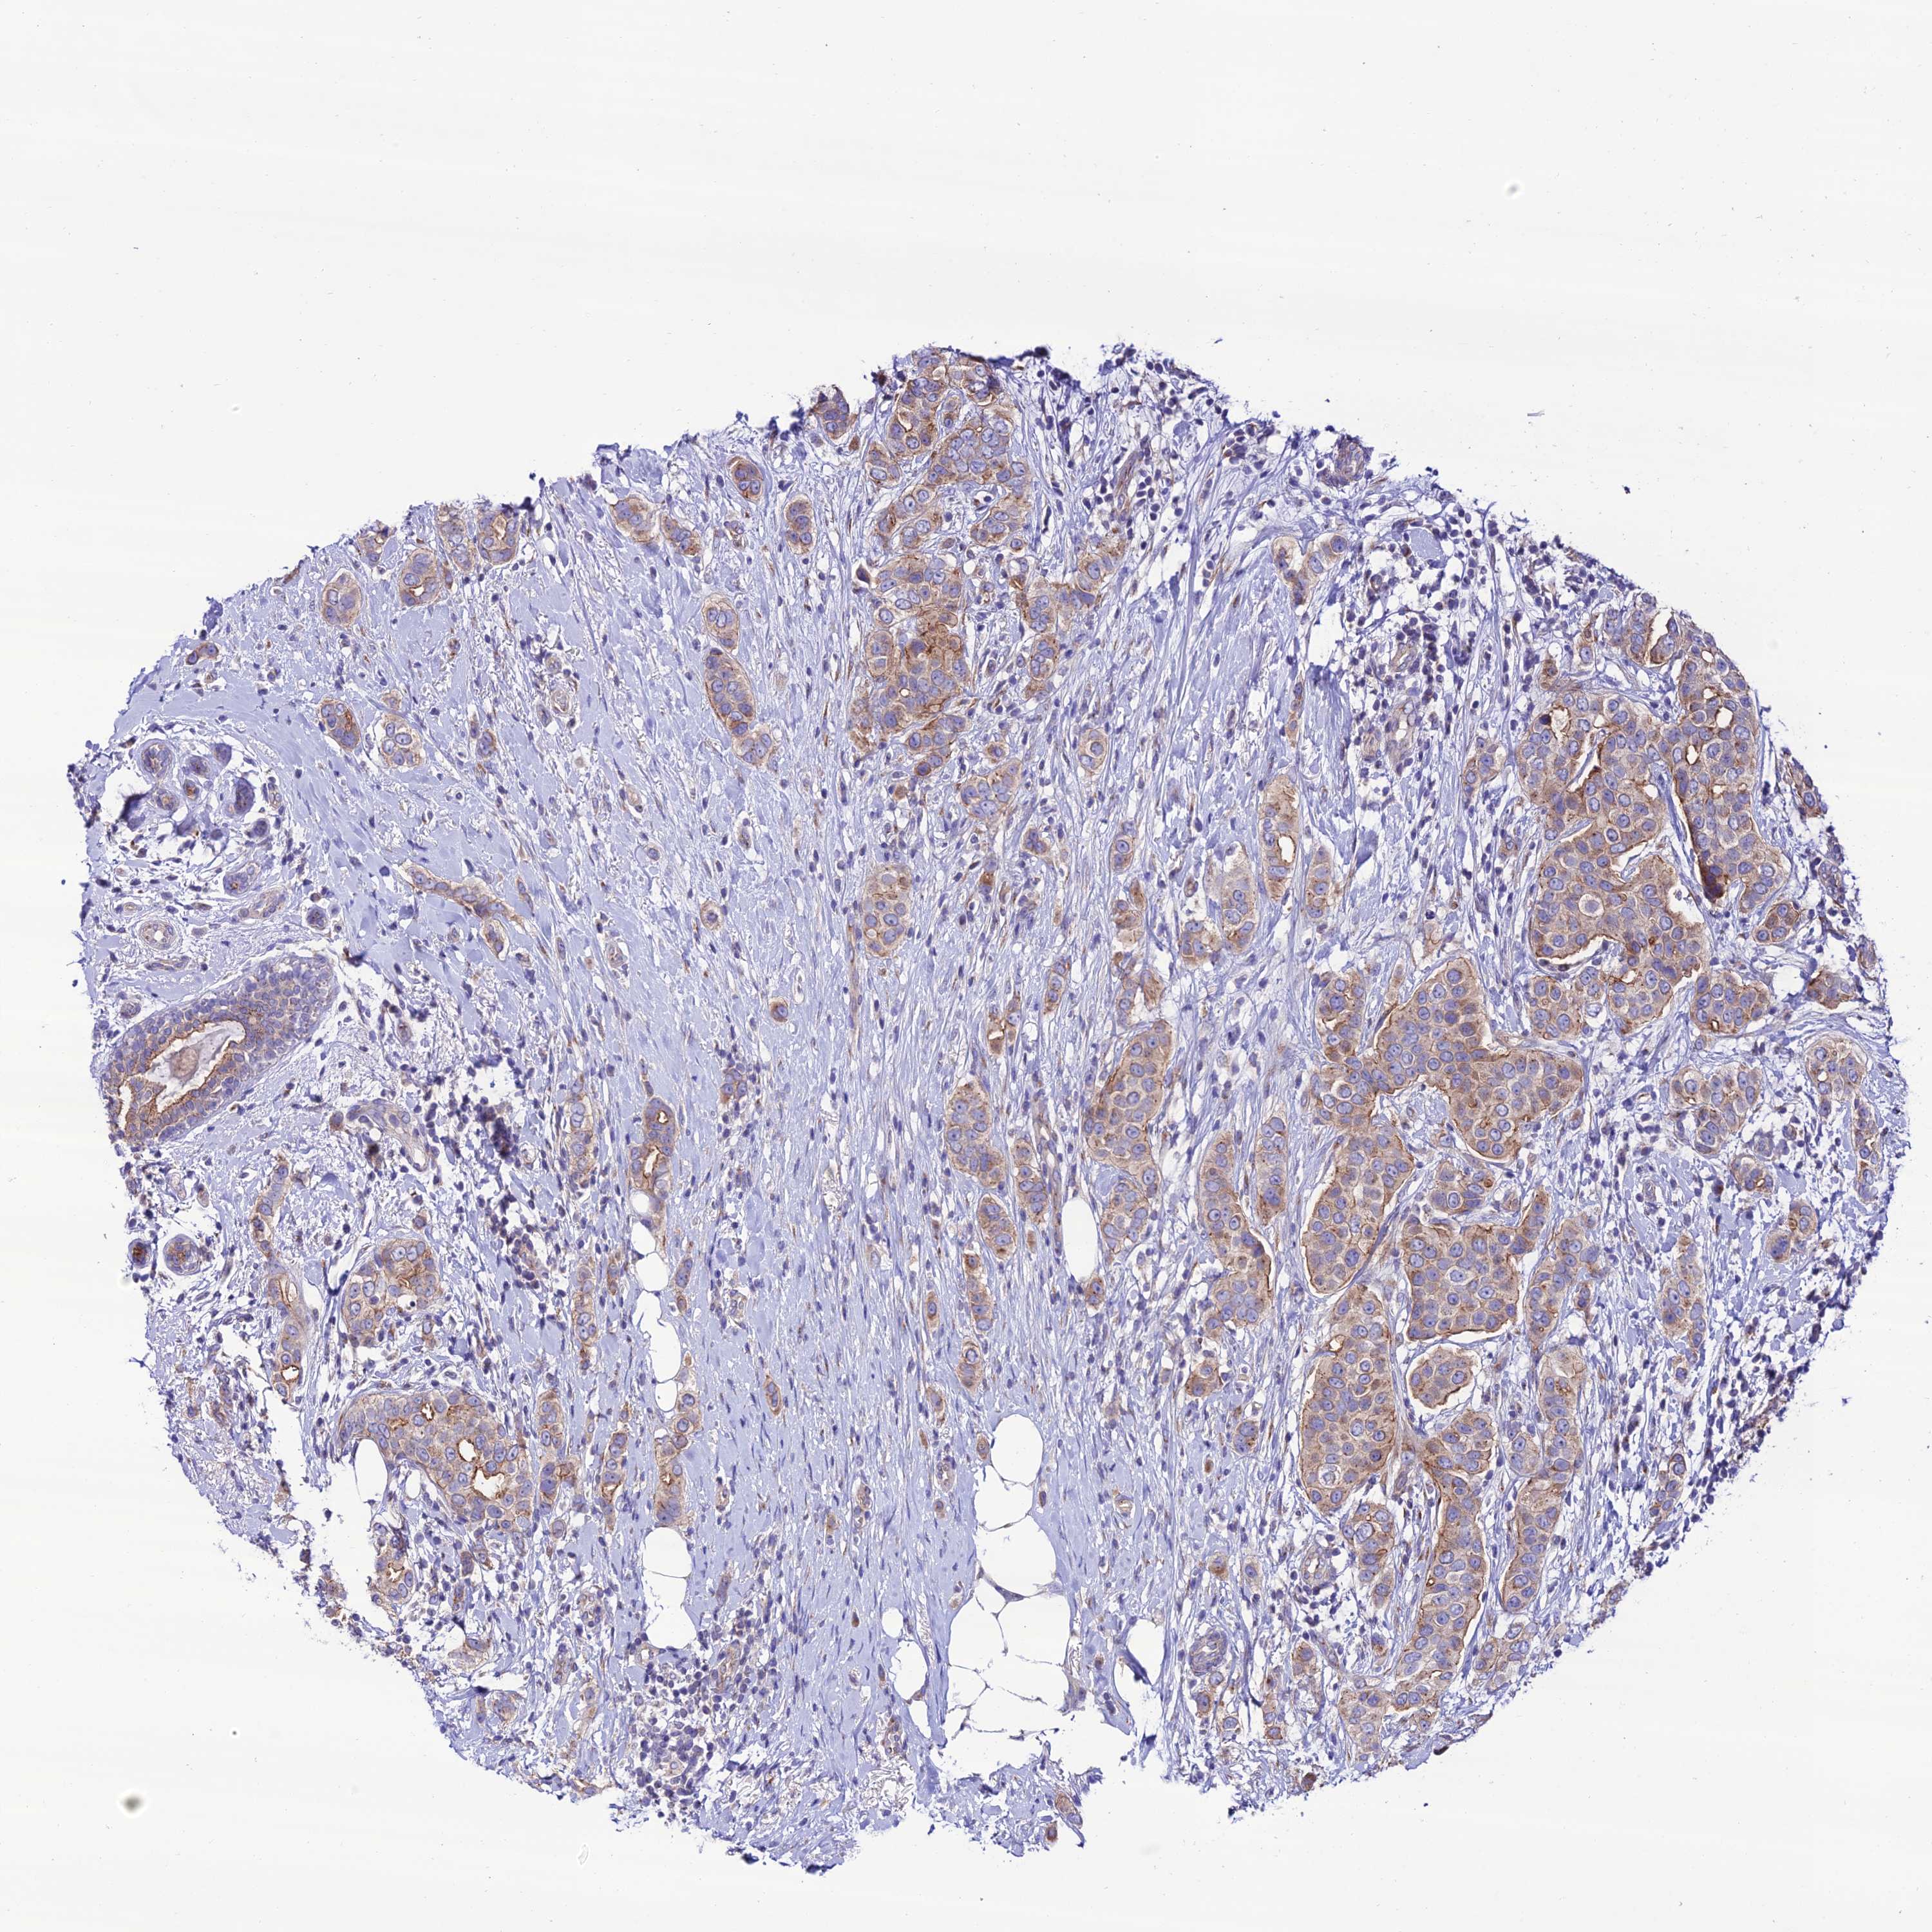

BRCA TCGA BRCA VALIDATION PROTEIN EXPRESSION